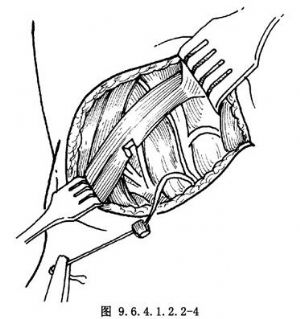

9.3 3.製備神經肌蒂

遊離胸鎖乳突肌前緣並牽向後,找到舌下神經襻至肩胛舌骨肌的分支(圖9.6.4.1.2.2-2),沿該分支向下分離至神經實際進入肌肉處,切取2~3mm3大小肌塊,連同神經一起保護備用(圖9.6.4.1.2.2-3,9.6.4.1.2.2-4)。